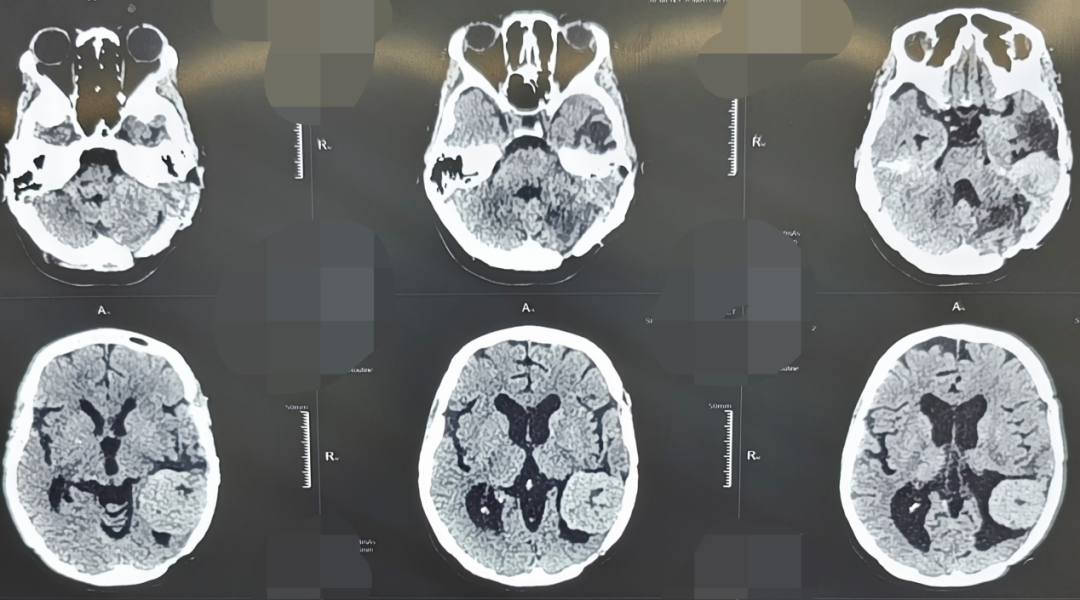

45岁的张女士,因“头晕、耳鸣伴听力下降”来到西安市红会医院就诊。她曾在2011年和2017年两次因颅内血管周细胞瘤于外院接受开颅手术治疗,并进行术后放化疗。此次入院后影像学检查显示,肿瘤在左侧颞部及桥小脑角区复发。该区域毗邻脑干、面神经、听神经及多条重要血管,素有“生命禁区”之称,手术风险极高。